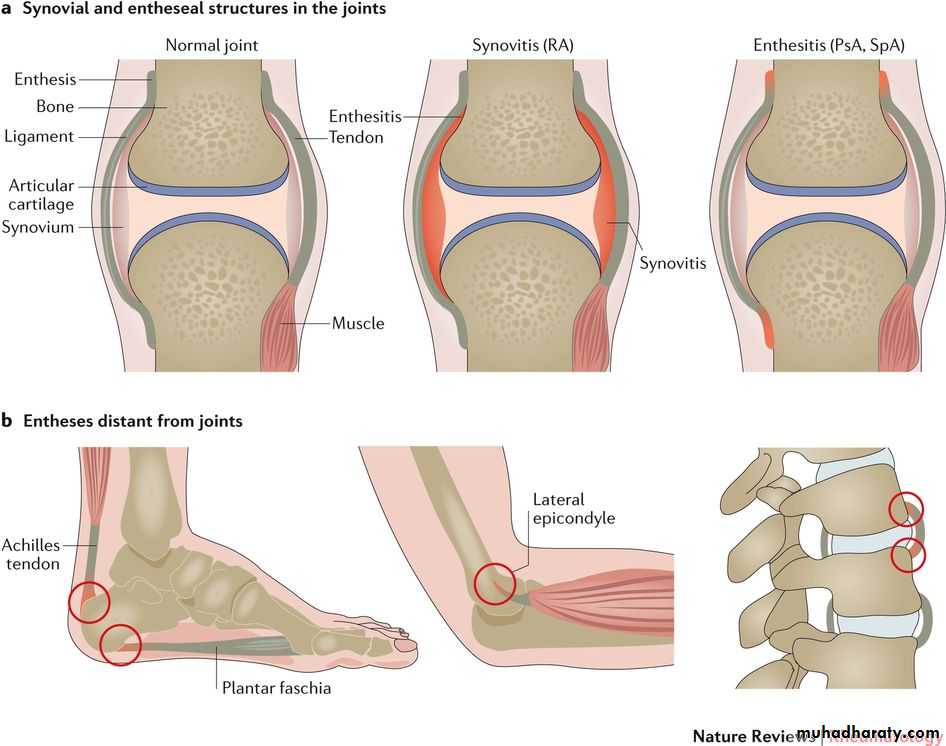

In contrast to RA, in the SpAs there are frequent and notable non-synovial musculoskeletal lesions – mainly inflammatory in nature – of ligaments, tendons, periosteum and other bone lesions.

A hallmark lesion of all SpAs is enthesitis, which is inflammation at the site of a ligament or tendon insertion into bone. Dactylitis, inflammation of a whole finger or toe, may also occur

Entheses that are typically affected include Achilles’ insertion, plantar fascia origin, patellar ligament entheses, gluteus medius insertion at the greater trochanter and tendon attachments at humeral epicondyles.